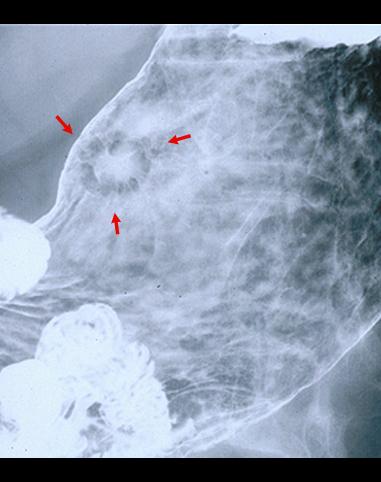

疾病(病理主体)的分类恶性上皮性肿瘤/腺癌

部位(按器官分)胃(部位)/体部

检查方法X线

肿瘤的肉眼分类0型(表在型)/IIc型(IIc)

肿瘤最大直径15~19

肿瘤的深度sm